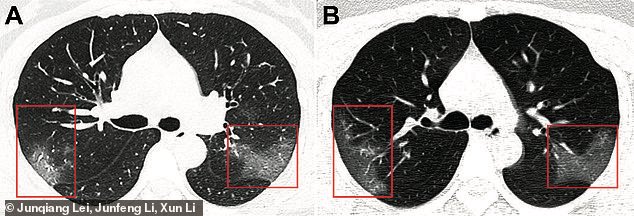

ويبدأ الضغط على الرئتين وذلك لكونها أصبحت ساحة المعركة الرئيسية، حيث ستنتفخ بالخلايا المناعية، والجزيئات والسوائل التي تستخدمها للتنقل وستقوم الخلية التائية القاتلة بالبحث عن الفيروس لتلتصق به وتقوم بقتله فورا، وتبدأ خلايا الدم البيضاء بابتلاع كمية كبيرة من جزئيات الفيروس الميته

وقد تتراكم هذه الخلايا على الرئتين ، ووجود هذه الخلايا على الرئتين سيسد مجاري الهواء وتقلل تدفق الأوكسجين .. وبالتالي سيسبب ضرر قوي على الشخص المصاب ، وسيمنعه من اخذ الاوكسجين الكافي ، وبالتالي سيحتاج الى أجهزة تنفس صناعية .. بعض الحالات تتأثر بشدة !

الأحداث السابقة سيكون عليها ضرر على الرئتين .. حيث هناك حالات حرجة سيعانون من ضرر دائم وقد تكون من ضمن من يعانون من أمراض مزمنة ، وحالات ستتعافى ولن يكون لديها سواء أنها عانت من إصابة سابقة من فايروس (كوفيد 19 / كورونا) !